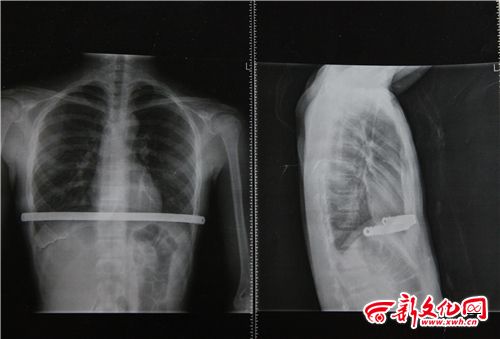

小博術(shù)后拍的CT片 本組圖片 新文化報 史磊 攝

家人懷疑小博的高燒與今年二月做的手術(shù)有關(guān),因為患有漏斗胸,小博做手術(shù)在體內(nèi)植入了鋼板。家人帶小博到北京的醫(yī)院檢查,檢查結(jié)果顯示各項指標都正常,不能確定小博高燒與之前的手術(shù)有關(guān)。